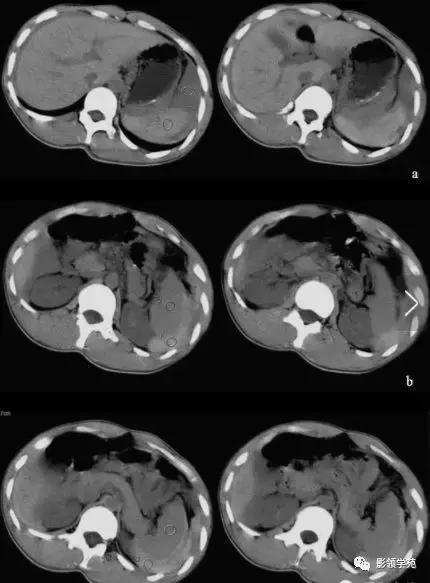

急性水肿型胰腺炎:CT平扫,胰腺明显肿胀,密度尚均匀,周围见条片渗出。

急性坏死型胰腺炎:CT平扫,胰腺密度不均匀减低,胰腺边界模糊,胰腺周围较多渗出积液,肝周可见积液。